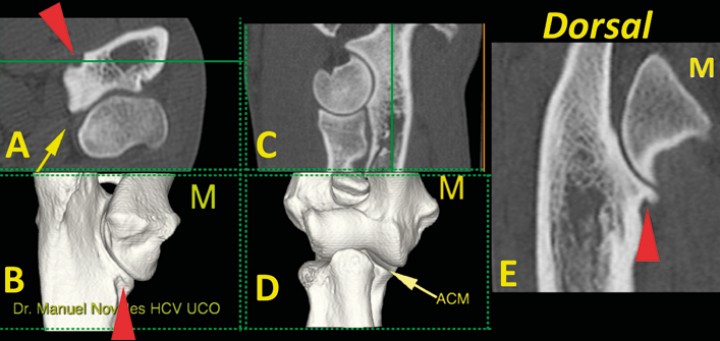

<p>Codo normal. Imágenes tridimensionales del codo en visión caudomedial (<strong>B</strong>) y craneal (<strong>D</strong>), así como planos de corte transversal (<strong>A</strong>), sagital (<strong>C</strong>) y dorsal (<strong>E</strong>). Las líneas verdes en A y C muestran el nivel al que se ha producido el plano dorsal (E). Se señala una escotadura normal (punta de flecha roja) que aparece en la porción medial de la ACM (flecha amarilla) (M: lado medial).</p>

Figura 7

Codo normal. Imágenes tridimensionales del codo en visión caudomedial (B) y craneal (D), así como planos de corte transversal (A), sagital (C) y dorsal (E). Las líneas verdes en A y C muestran el nivel al que se ha producido el plano dorsal (E). Se señala una escotadura normal (punta de flecha roja) que aparece en la porción medial de la ACM (flecha amarilla) (M: lado medial).

En el plano dorsal nos fijamos en tres zonas de corte concretas: a) la escotadura troclear del cúbito (Fig. 6); b) el ápex de la ACM, que debe ser cóncavo por su cara medial (Fig. 7); y c) la base de la ACM (Fig. 8). En este plano de corte debemos valorar: 5) ACM (mediante avance del corte dorsal para valorar una posible línea de fragmentación); 6) la unión completa de las caras medial y lateral del cóndilo humeral en su zona media; 7) la morfología normal del hueso subcondral del cóndilo humeral y su grado de esclerosis; 8) la congruencia articular humero-radial y húmero cubital; 9 y 10) y la ausencia de osteofitos o enteseofitos en las caras medial y lateral del codo (Figs. 7, 8 y 9) (Vídeo 3).